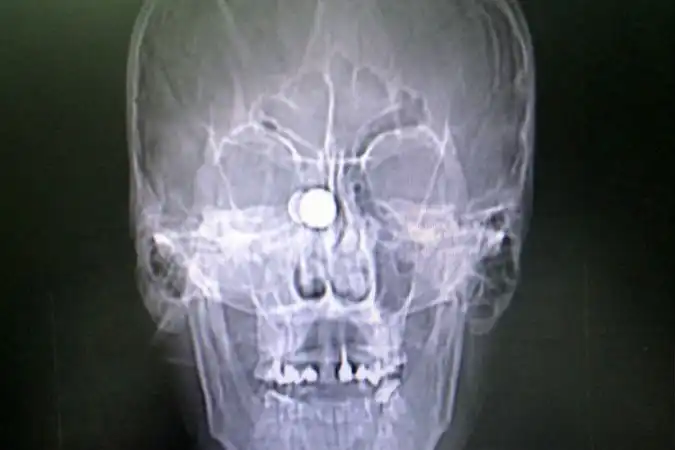

Сначала раненного доставили в глазной центр, где врачи удалили глазное яблоко. Потом перевели в краевую больницу. Отолорингологи краевой больницы провели, по сути, уникальную операцию высокотехнологичную операцию, чтобы извлечь из головы пациента пулю размером с орех. Самое опасное, что она находилась прямо в миллиметре от мозга молодого мужчины.

- Инородный предмет врачи ювелирно удалили под микроскопом, с применением эндоскопа через носовое отверстие, — рассказали в пресс-службе Краевой клинической больницы. — В настоящее время состояние пациента не вызывает у врачей опасений за его жизнь.